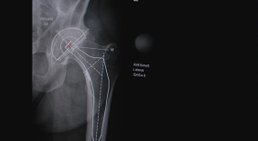

Künstliches Hüftgelenk (nach der minimal invasiven AMIS-Methode)

Rheumatische Erkrankungen, eine dauerhafte Überbelastung, Verletzungen und Übergewicht können zu einer Hüftgelenksarthrose, auch Coxarthrose genannt, führen....